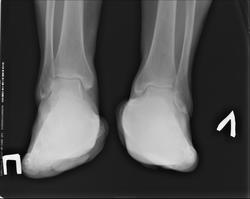

Пол пациента: Женский пол Тип патологии: Воспалительное заболевание неинфекционной природы Область исследования: Скелетно-мышечная система Методы исследования: Rg Женщина страдает ревматоидным артритом длительное время. Ортопед выставил диагноз- вторичный деформирующий артроз левого голеностопного сустава. Рекомендует реконструктивную операцию. Прошу помощи в описании снимков и определении степени поражения. https://radiomed.ru/sites/default/files/styles/case_slider_image/public/user/18854/zayceva_nogin_a_0.jpg?itok=IXEIKgIg ID:31630 Чт, 12/09/2013 - 12:12 #1 Нюра Не на сайте Был на сайте: 11 лет 4 месяцев назад Зарегистрирован: 12.09.2013 - 11:45 Публикации: 8 Прошу прощения за косяки ,первый раз на сайте, еще не научилась правильно оформлять сообщения Чт, 12/09/2013 - 12:11 #2 Helios Не на сайте Был на сайте: 7 месяцев 2 недели назад Зарегистрирован: 06.08.2010 - 15:16 Публикации: 4417 Нюра, исправила. Не забывайте нажать на волшебную кнопочку "вставить" Чт, 12/09/2013 - 12:15 #3 Нюра Не на сайте Был на сайте: 11 лет 4 месяцев назад Зарегистрирован: 12.09.2013 - 11:45 Публикации: 8 благодарю за помощь Чт, 12/09/2013 - 12:24 #4 Helios Не на сайте Был на сайте: 7 месяцев 2 недели назад Зарегистрирован: 06.08.2010 - 15:16 Публикации: 4417 Чт, 12/09/2013 - 15:44 #5 ЛГ Не на сайте Был на сайте: 8 лет 10 месяцев назад Зарегистрирован: 06.01.2010 - 12:31 Публикации: 3523 Не вижу рентгенологических признаков артроза. https://www.youtube.com/channel/UCBGxoBUOqUT_bFhSeUgtWEw Чт, 12/09/2013 - 15:51 #6 maker4ik Не на сайте Был на сайте: 8 лет 6 месяцев назад Зарегистрирован: 19.10.2011 - 17:49 Публикации: 2682 Что за реконструктивные операции такие при ДОА голеностопного сустава? Никогда не слышала. Пт, 13/09/2013 - 05:47 #7 Нюра Не на сайте Был на сайте: 11 лет 4 месяцев назад Зарегистрирован: 12.09.2013 - 11:45 Публикации: 8 спасибо за ответ

Не вижу рентгенологических признаков артроза.